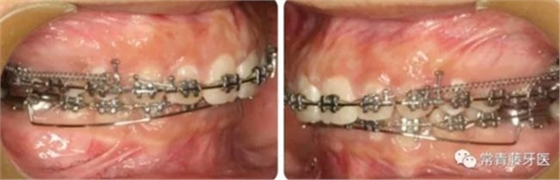

A67、B67之間植入微種植釘整體內(nèi)收上牙列,下頜配合多用途弓整平牙列改善覆合。

繼續(xù)內(nèi)收上牙列,此時(shí)下頜spee曲線基本整平。